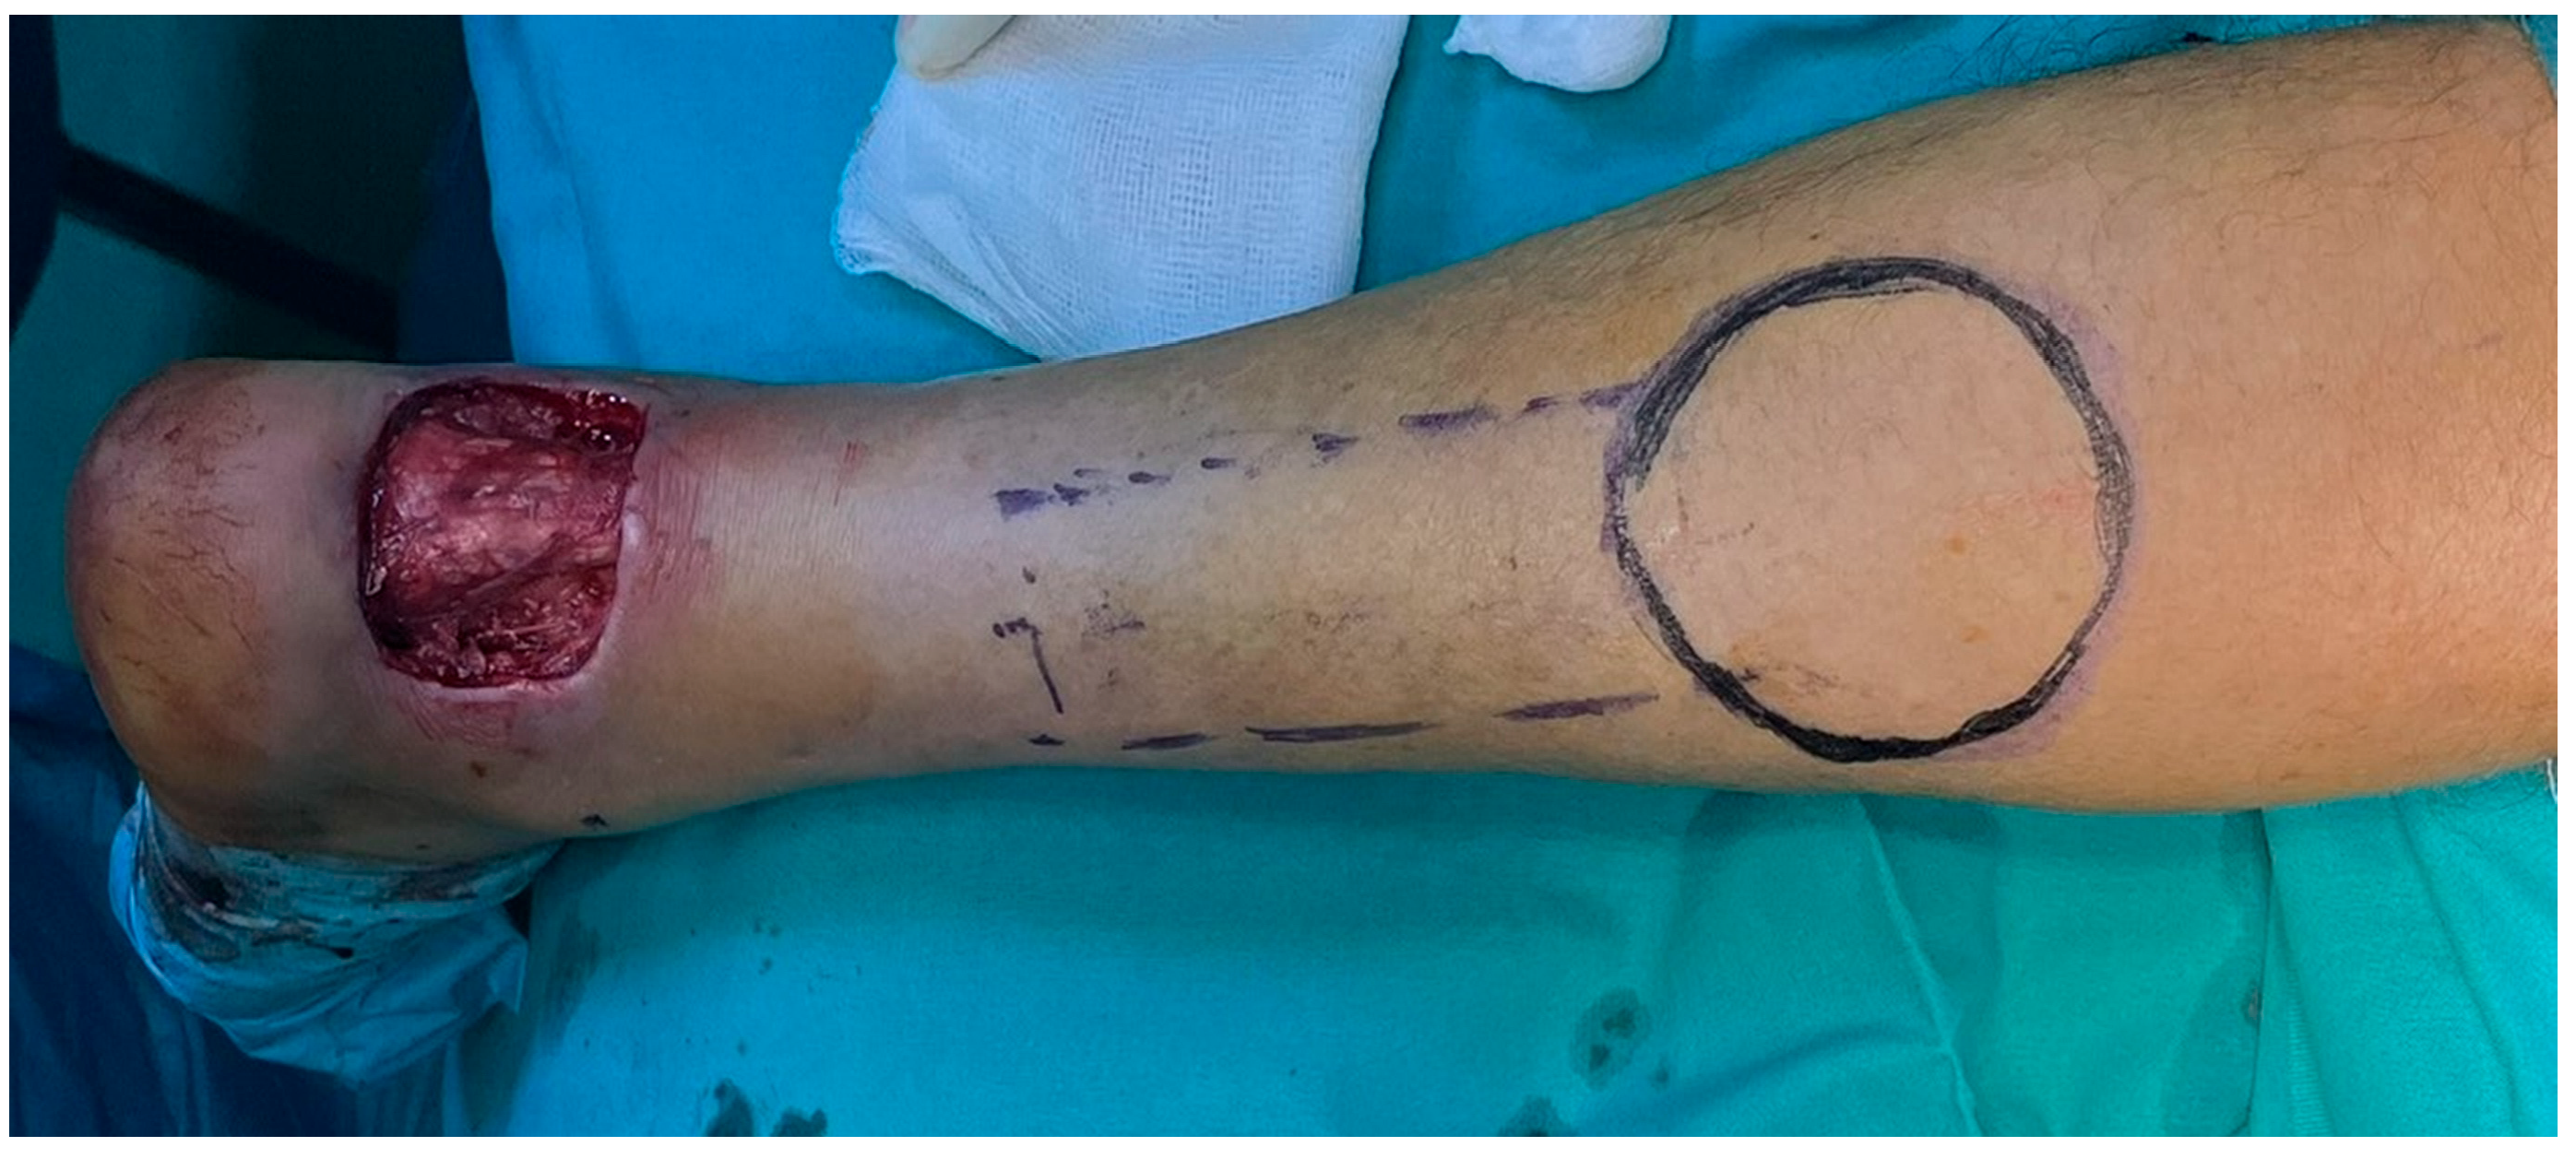

After debridement of the necrotic area, the soft tissue defect was about 6 cm × 7 cm. Figure 9. The fracture was reduced and fixed through the ORIF method with two canulated screws. Figure 10.

The soft tissue defect was treated with a local reverse sural flap. The pedicle of the flap was 4 cm wide. The flap was dissected, and the pedicle was dissected, and the flap was pivoted to the defect through a tunnel under the skin. The tunnel was performed in the supra-fascial plane, 9 cm long and 5 cm wide. The donor site was covered with STSG. Postoperatively, there was no concern regarding the blood flow to the flap. Figure 11.

Figure 9. (A) debridement of the necrotic area. (B) final soft-tissue defect. The bone fragment can be seen (red arrow) protruding through the defect.

Figure 11. Intraoperative design of the flap.